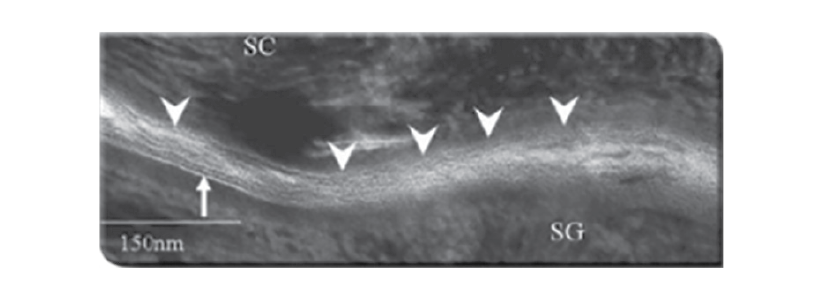

Після лікуваннябетаметазоном:

SC – роговий шар SG – зернистий шар ТКС – топічні кортикостероїди

Трансмісійна електронна мікроскопія перехідної зони між зернистим і роговим шаром

відсутня нормальна структура шкірного

бар’єру та суцільного біліпідного шару

зовнішньої мембрани7